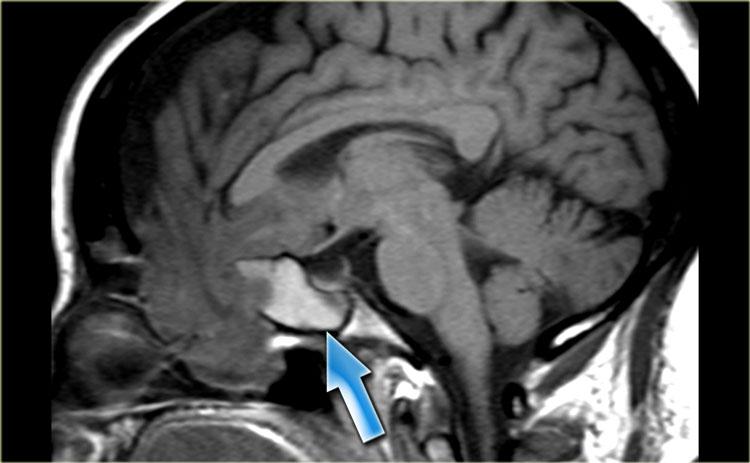

Một biến chứng hiếm gặp của phẫu thuật nội soi xoang chức năng (FESS) được thấy trong các hình ảnh bên trái.

Đơn vị Hounsfield của các bất thường nhỏ mà dấu hoa thị chỉ vào vào khoảng -120.

Trước tiên hãy quan sát các hình ảnh mặt phẳng axial.

Sau đó tiếp tục với các hình ảnh mặt phẳng coronal.

Có khuyết xương tại trần sàng (fovea ethmoidalis) (mũi tên đỏ).

Ngoài ra còn có các thay đổi sau phẫu thuật cho thấy bệnh nhân đã trải qua phẫu thuật FESS.

Khí nội sọ là biến chứng của phẫu thuật FESS.

Với biến chứng này, thông thường bệnh nhân ra về trong tình trạng ổn định, sau đó tái nhập viện khoảng hai tuần sau với tình trạng rò dịch não tủy và viêm màng não, do khuyết xương và màng cứng.

Tràn khí nội sọ áp lực xảy ra khi khí trong hộp sọ hoạt động như một khối choán chỗ: có khuyết xương cho phép khí đi vào nhưng không thoát ra được (chức năng như van một chiều).

Mỗi lần bệnh nhân hắt hơi, khí bị đẩy qua chỗ khuyết vào khoang nội sọ và bị giữ lại ở đó.

Đến một thời điểm nhất định, lượng khí đủ lớn để gây hiệu ứng khối lên các cấu trúc nội sọ xung quanh.